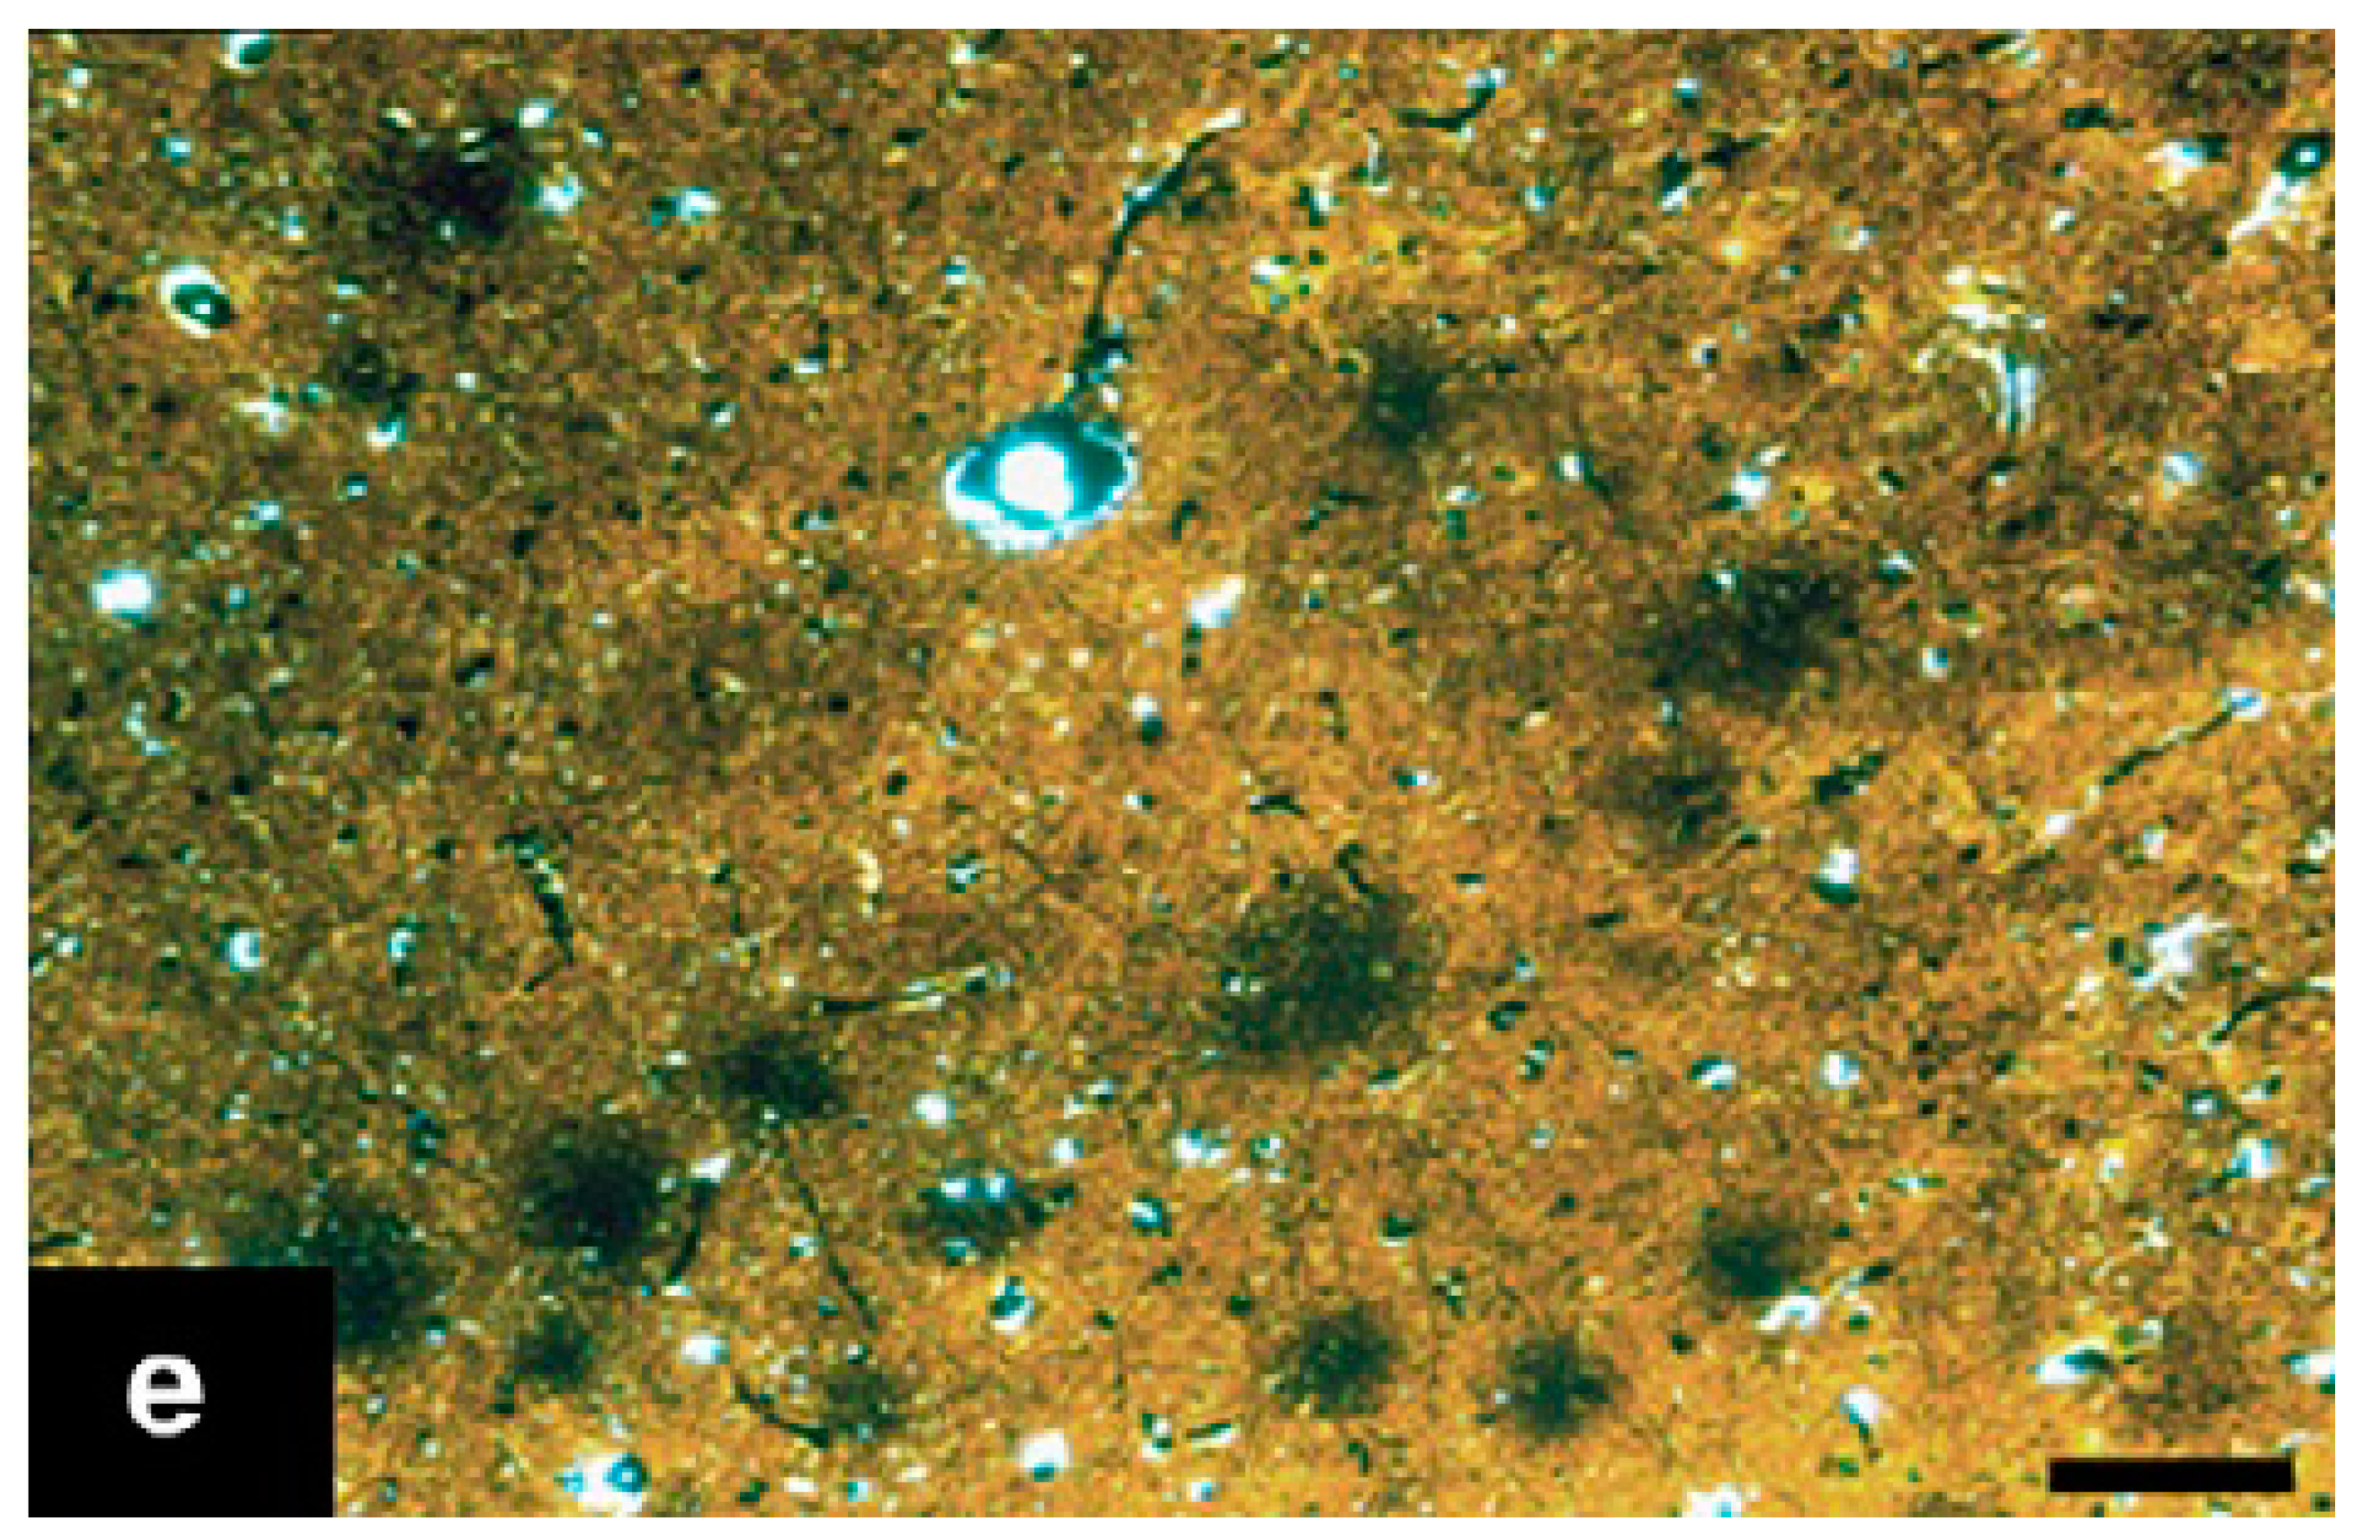

| Alzheimer’s-like disease | Domestic cat | Aβ oligomers aggregates in cats aged 8 and more Senile plaques in cats aged 10 and more NFTs only in the presence of Aβ Neuronal loss Neuronal degradation | Spatial disorientation or confusion Altered social relationships Intensified aggression or passiveness Changes in daily schedule and wake-sleep pattern Changes in interest in food Decreased grooming Inappropriate vocalization | [66,67,68,69,70,71] |

| Canine Cognitive Dysfunction (CCD) | Dog | Cortical atrophy Dysfunction in the neurotransmitter systems Increased oxidative damage Extracellular deposition of diffuse Aβ Neuronal loss Decreased neurogenesis Tau abnormalities, but not NFTs Ventricular enlargement Oligomers of Aβ in the CSF | Loss of cognition and recognition Loss of house training Disorientation Changes in their sleep-wake cycle | [74,75,76,77,78,79,80,81,82,84,85,86] |